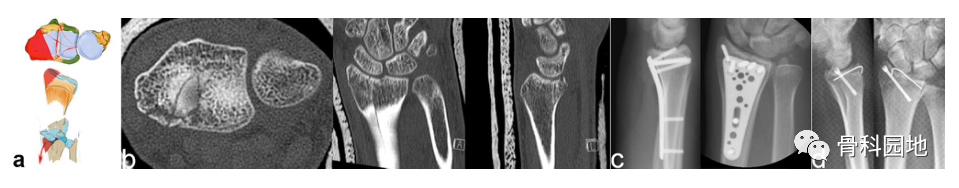

注:可以是大的或较小的边缘碎片。可能发生掌侧脱位,而背侧韧带保持完整 (a)。掌侧骨块:重要的尺桡韧带和尺腕韧带的起源 (b)。向掌侧脱位(c)。掌侧骨折从尺侧延伸到桡侧(d)。在 X 光平片上很容易忽略小的掌侧尺骨骨块,但轴位 CT 扫描容易显示该骨块 (e)

3、背侧关键骨块施加在背侧方向的作用力不仅会导致桡骨背侧骨折, 而且还会使腕关节背侧脱位。

注:背侧脱位,背侧外部插入。手掌韧带断裂(a)。普通 X 射线显示背侧脱位的程度。然而,在 CT 扫描中,可以看到关节面的额外凹陷、S 状切迹的台阶和背键骨块 (b)。背侧骨块不一定是关键骨块。如左两个图像所示。尽管背侧脱位,但掌侧骨折块仍附着在掌侧韧带装置上,这个由骨韧带组成的掌侧关键骨折块需要特别注意,必须首先固定,如图所示(c)